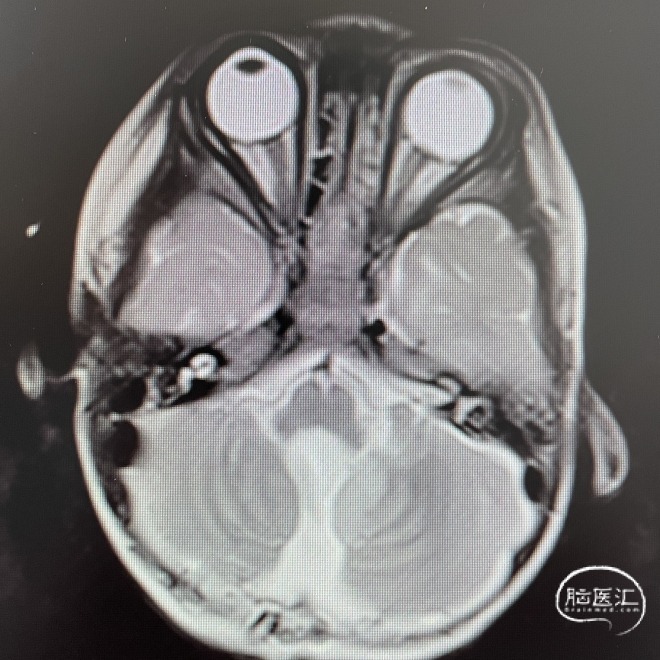

影像学资料

头部MRI检查:第四脑室扩大,其内可见一类圆形肿块,呈稍长T1稍长T2信号,边界清楚,较大截面范围约47*35*48mm。增强后呈不均匀强化;病灶向下延伸至颈段椎管内,向两侧孔延伸至桥小脑角区。幕上脑室系统扩大,周围可见片状长T1长T2信号。

术前